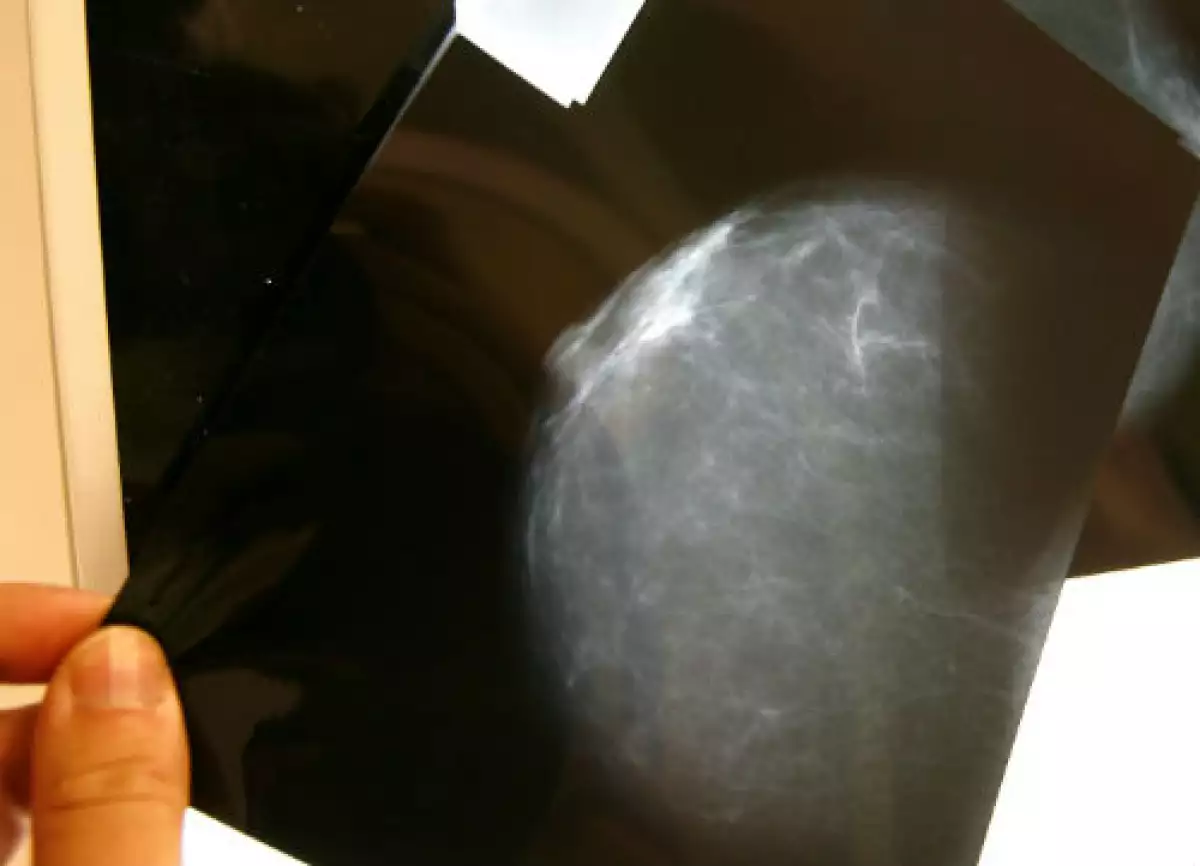

Hace un año, Ríos, junto con cuatro compañeros más, se dio a la tarea de desarrollar una solución que pudiera ser más certera que la autoexploración y menos peligrosa que las mamografías, que según la National Breast Cancer Foundation y a un estudio publicado en el British Medical Journal, la radiación, así como la comprensión que causa este tipo de técnicas pueden provocar la propagación de células cancerígenas a otras partes del cuerpo, con lo que se causa metástasis.